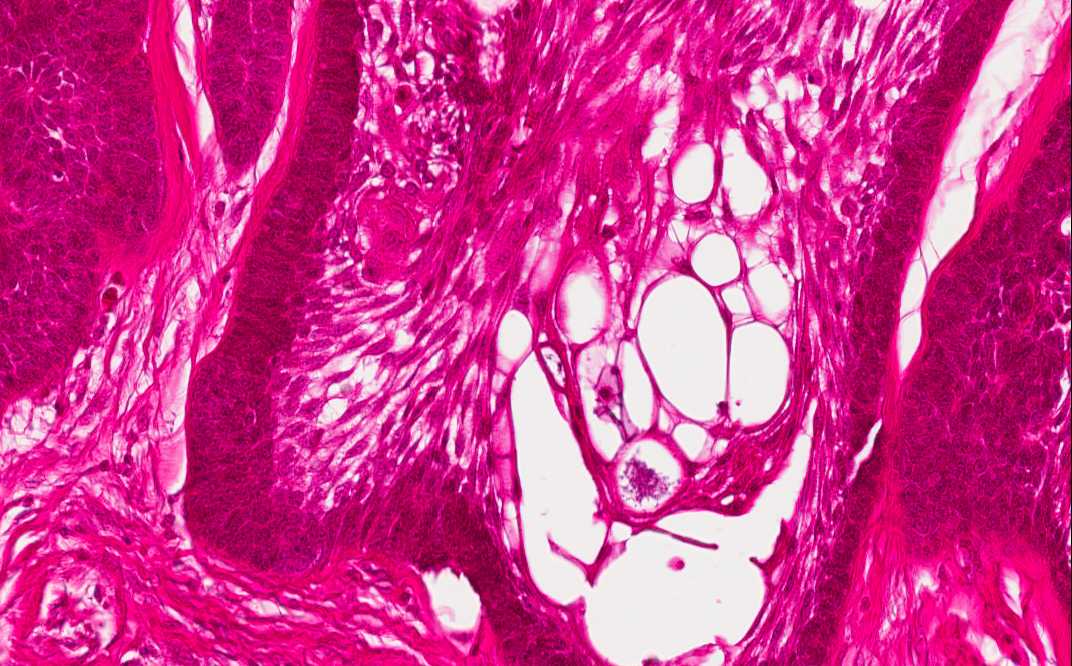

Area 2: Note that the cyst are lined by palisading columnar cells with reversed polarity. Cyst formation is very common in ameloblastomas. Some of the cyst may be, at least partially, lined by attenuated squamous epithelium that lacks features of ameloblasts.

Histologic Highlights of this Case:

• In Area 2, cyst formation is present. The cysts are lined by the cells with pseudopalisading pattern similar to that of area 1.

• The overall nuclear features are bland and without significant pleomorphism or high grade atypia. Mitotic figures are not readily seen.

• Note that the specimen appears more eosinophilic than other specimens being shown in this program. This is because the specimen has to be decalcified before examination and slightly over decalcified specimens often appear more eosinophilic and the nuclear details are not as well preserved.